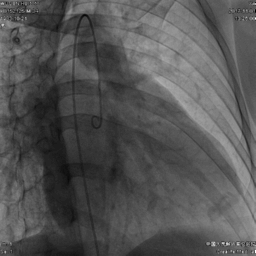

06造影下的心脏